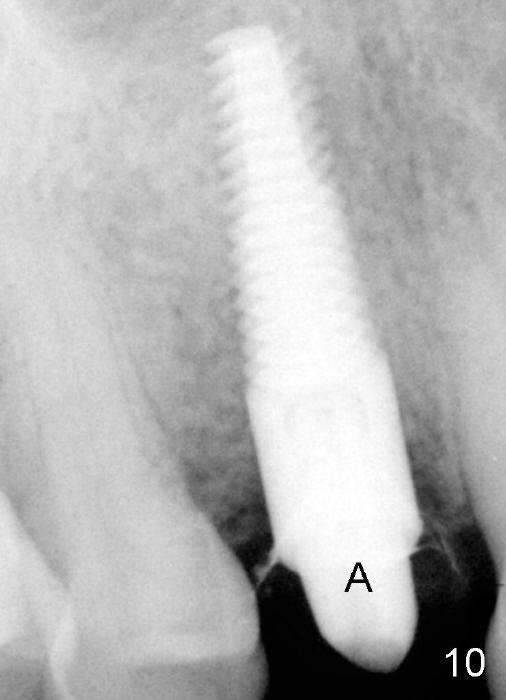

The patient returns 6 months postop for impression of a permanent restoration. The gingiva with knife-edged papillae adapts to the provisional (Fig.7). The gingiva looks healthy when the provisional is removed (Fig.8). The buccal bone resorption seems to be minimal, as compared to Fig.1,2. There is no bone loss between immediately postop (Fig.9 I; implant), 4.5 months postop (Fig.10 A: abutment), 4 and 7 months post cementation (Fig.11,12 C: crown). Soft and hard tissue morphology remains normal 7 months post cementation (Fig.13). No bone loss is observed 15 months post cementation (Fig.14). The papillae (Fig.15) and bone (Fig.16,17) remain stable 29 months post cementation.